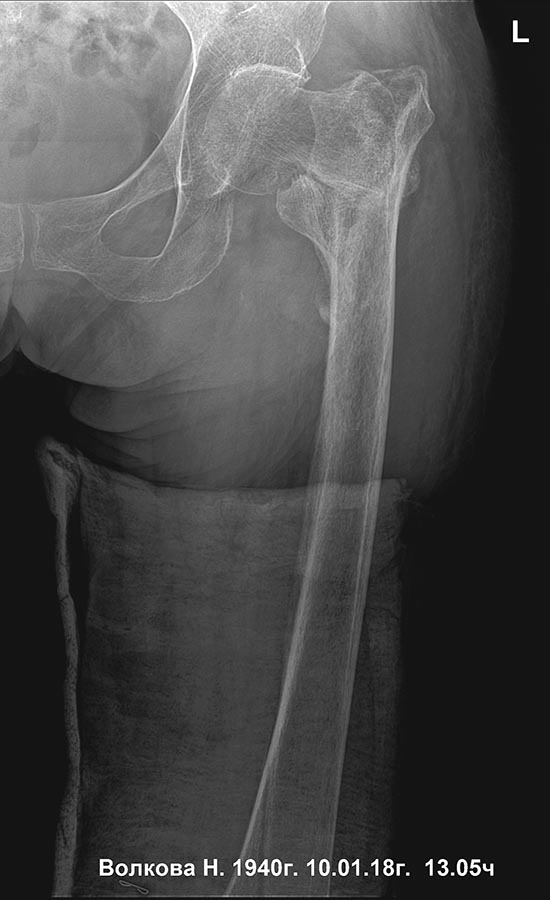

Сросшийся чрезвертельный и перелом н\3 бедра |

Уважаемые коллеги, прошу высказаться по такому случаю, 4 мес назад чрезвертельный перелом, 2 нед назад при попытке ходьбы с ходункамии нога подкосилась (укороч порядка 4-5 см), и пациентка сломала нижнюю треть. Какие мнения, как сделать поаккуратнее, бабушка 78 лет. Состояние здоровья среднее.

линия как будто проходит через наружный мыщелок

нижняя треть

Нижняя треть - - это про диафиз. А тут, похоже, перелом наружного мыщелка бедра. Да, одним гвоздем тут тогда не стоит пытаться. Это две разные проблемы. Дейстительно, для дистального перелома подойдет соответствующая пластина. А в проксимальном отделе - короткий PFN после вальгизации.

снимок с максимальным приведением